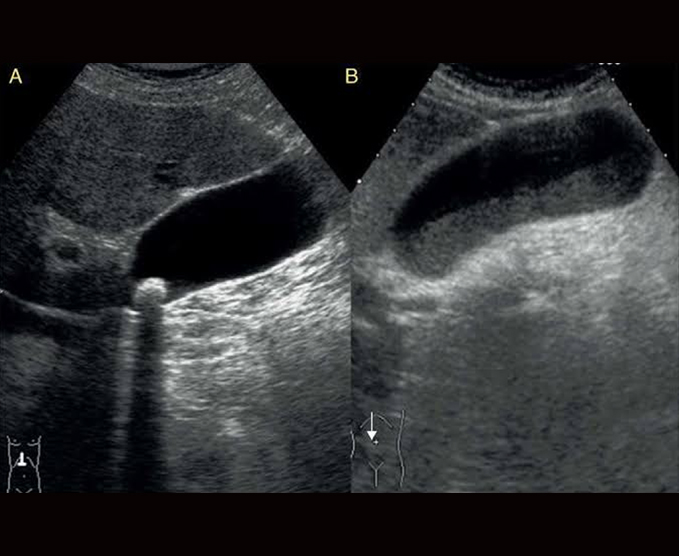

Es una prueba diagnóstica que utiliza ondas sonoras de alta frecuencia que hacen contacto con los órganos y que son convertidas automáticamente en imágenes de la zona explorada.

Normalmente se realiza a través de la piel, aplicando un gel acuoso que sirve de contacto a un dispositivo llamado transductor, el cual se mueve por la zona a explorar mientras el médico radiólogo puede observar en tiempo real las imágenes que se generan en el monitor del ecógrafo.

- Ultrasonido renal

- Ultrasonido hepatobiliar

- Ultrasonido de abdomen